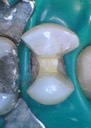

Joe Cha #20 finish